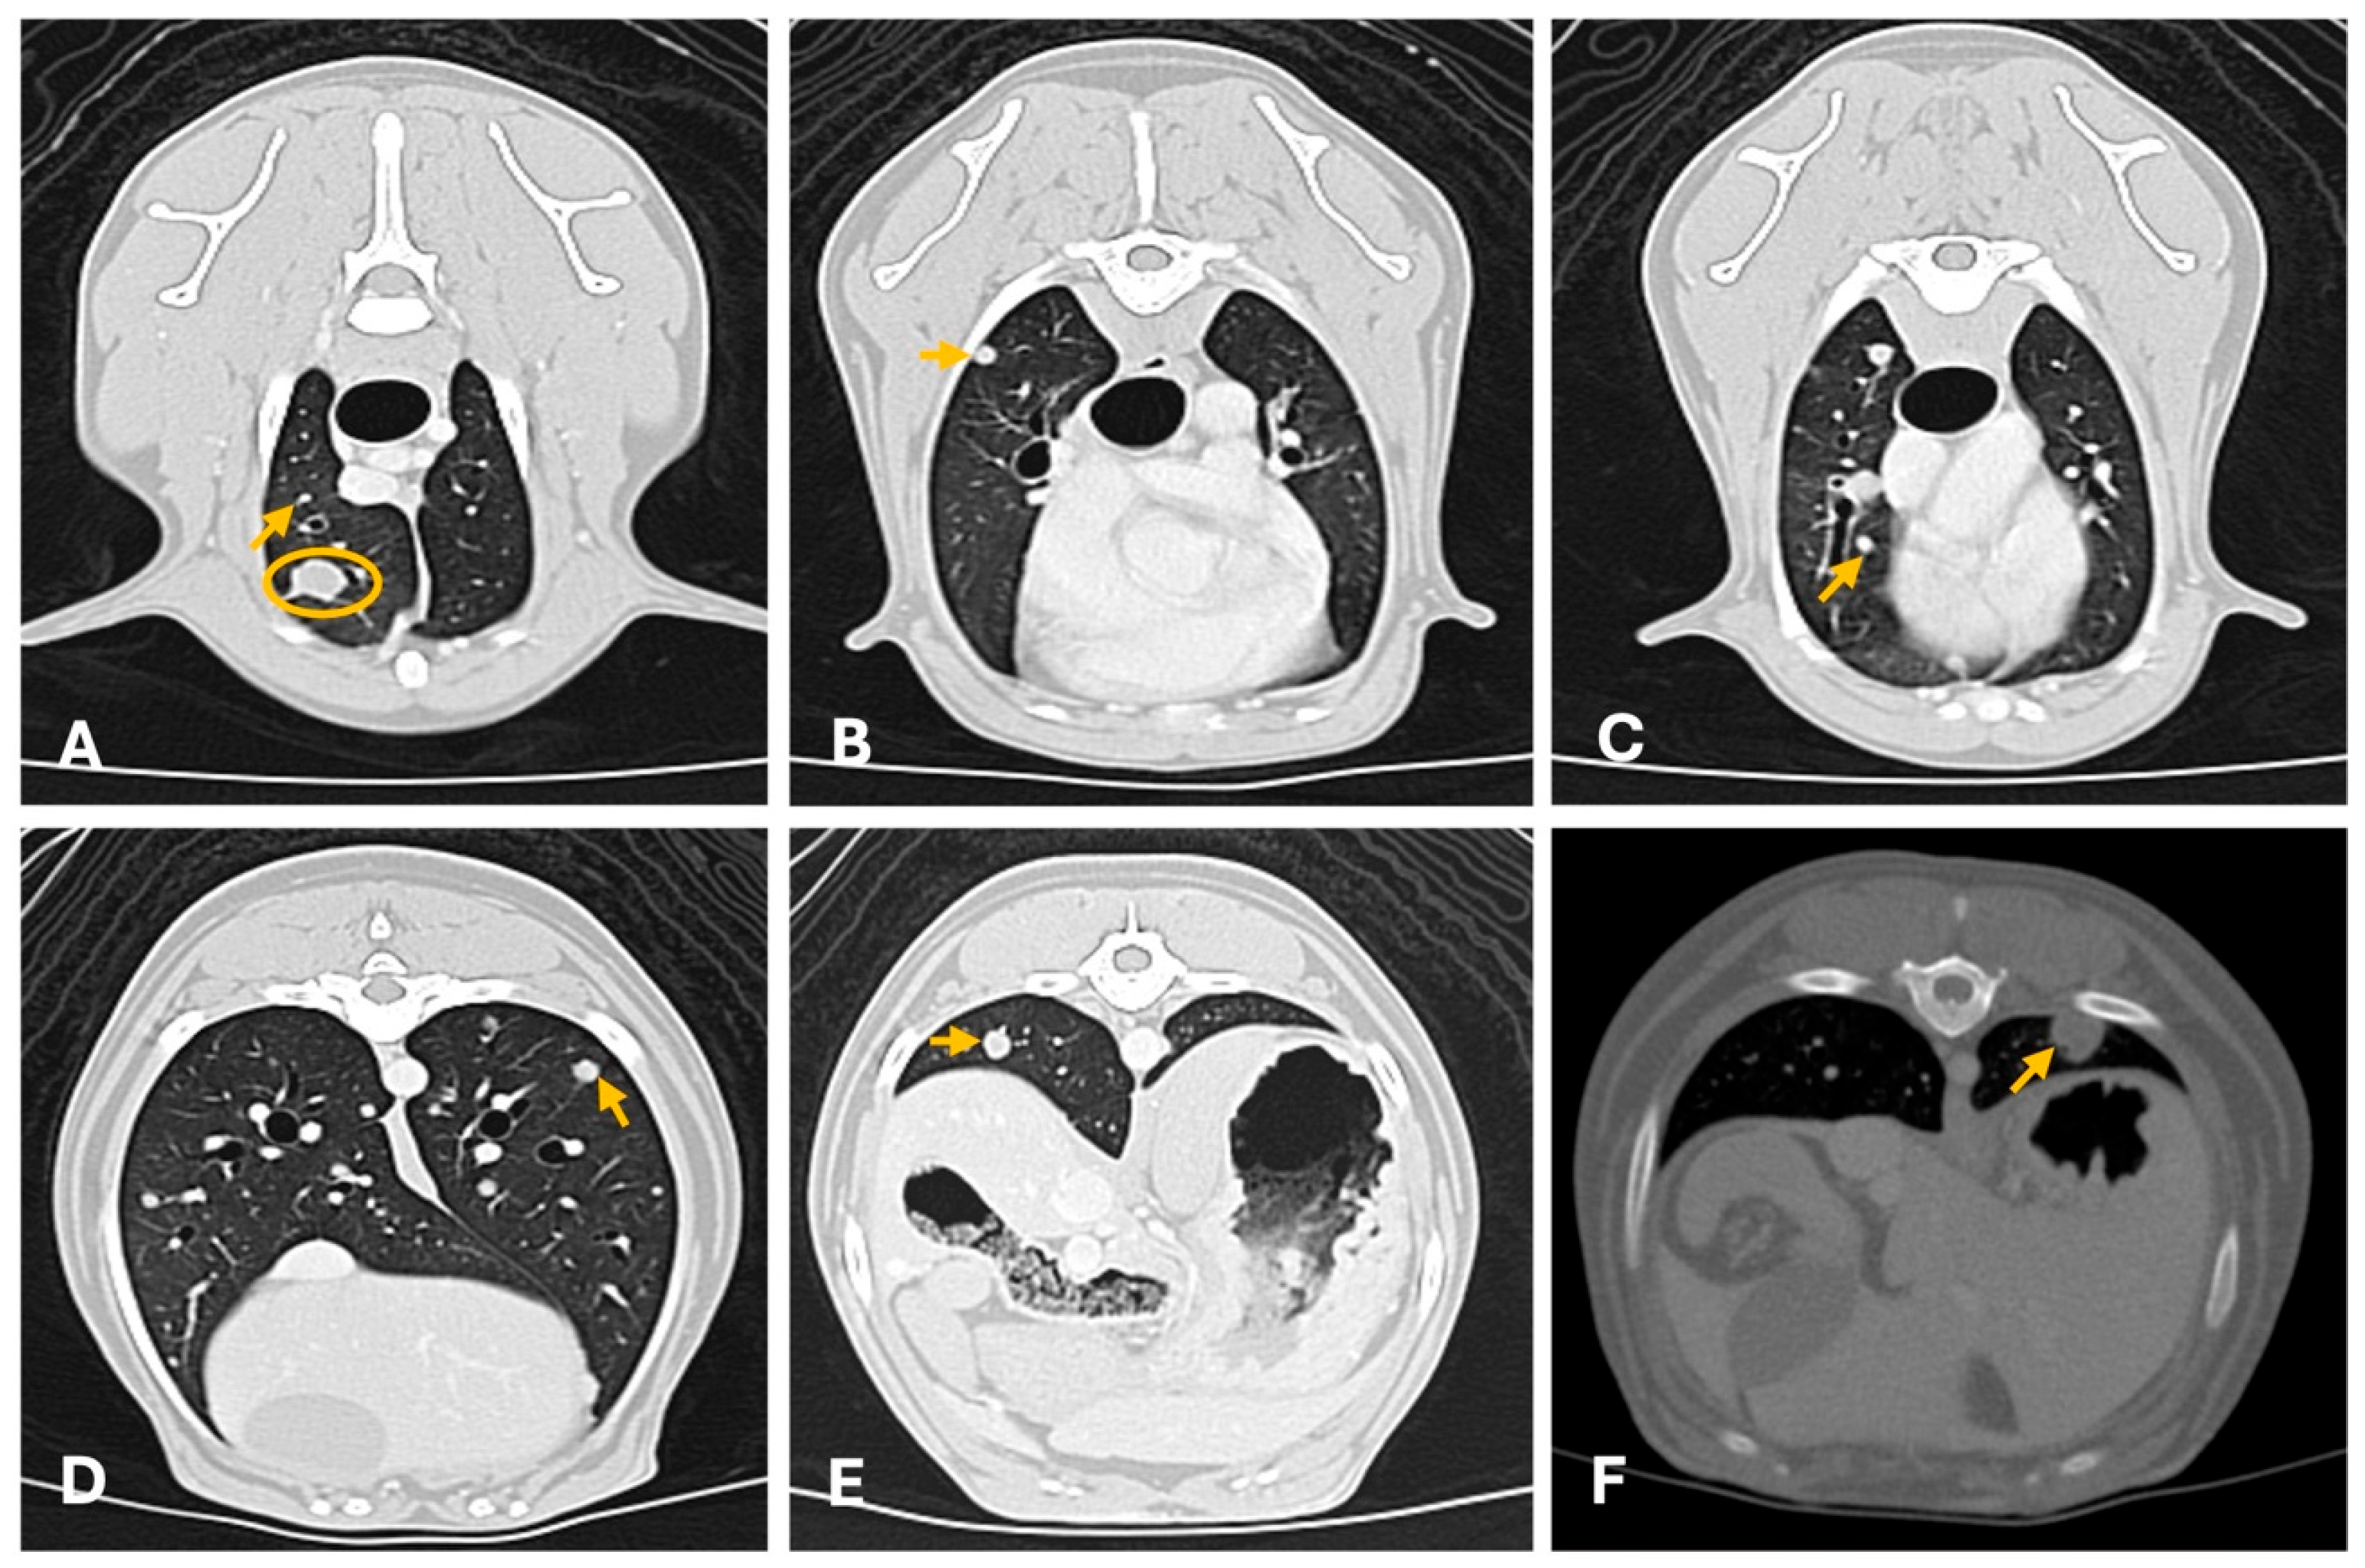

3.2. Computed Tomography

4.2. Computed Tomography

- Lamb, C.R.; Whitlock, J.; Foster-Yeow, A.T.L. Prevalence of Pulmonary Nodules in Dogs with Malignant Neoplasia as Determined by CT. Vet. Radiol. Ultrasound 2019, 60, 300–305. [Google Scholar] [CrossRef]

- Miles, K.G.; Lattimer, J.C.; Jergens, A.E.; Krause, G.F. A retrospective evaluation of the radiographic evidence of pulmonary metastatic disease on initial presentation in the dog. Vet. Radiol. 1990, 31, 79–82. [Google Scholar] [CrossRef]

- Armbrust, L.J.; Biller, D.S.; Bamford, A.; Chun, R.; Garrett, L.D.; Sanderson, M.W. Comparison of Three-View Thoracic Radiography and Computed Tomography for Detection of Pulmonary Nodules in Dogs with Neoplasia. J. Am. Vet. Med. Assoc. 2012, 240, 1088–1094. [Google Scholar] [CrossRef]

- Klaengkaew, A.; Sutthigran, S.; Thammasiri, N.; Yuwatanakorn, K.; Thanaboonnipat, C.; Ponglowhapan, S.; Choisunirachon, N. The Evaluation of Non-Anesthetic Computed Tomography for Detection of Pulmonary Parenchyma in Feline Mammary Gland Carcinoma: A Preliminary Study. BMC Vet. Res. 2021, 17, 237. [Google Scholar] [CrossRef] [PubMed]

- Otoni, C.C.; Rahal, S.C.; Vulcano, L.C.; Ribeiro, S.M.; Hette, K.; Giordano, T.; Doiche, D.P.; Amorim, R.L. Survey Radiography and Computerized Tomography Imaging of the Thorax in Female Dogs with Mammary Tumors. Acta Vet. Scand. 2010, 52, 20. [Google Scholar] [CrossRef]

- Lekshmi, S.L.; Nair, S.S.; Sajitha, I.S.; Ramankutty, S.; Narayanan, M.K.; John Martin, K.D. Radiographic Assessment of Pulmonary Metastatic Lesions in Superficial Cutaneous and Mammary Neoplasms in Dogs. J. Vet. Anim. Sci. 2021, 52, 393–398. [Google Scholar] [CrossRef]

- Forrest, L.J.; Graybush, C.A. Radiographic Patterns of Pulmonary Metastasis in 25 Cats. Vet. Radiol. Ultrasound 1998, 39, 4–8. [Google Scholar] [CrossRef]

- Fonseca Pinto, A.C.B.C.; Iwasaki, M.; Figueiredo, C.M.; Cortopassi, S.R.G.; Sterman, F.d.A. Tomografia Computadorizada do Tórax de Cadelas Portadoras de Neoplasias Malignas. II—Avaliação dos Campos Pulmonares. Braz. J. Vet. Res. Anim. Sci. 2007, 44, 174–182. [Google Scholar] [CrossRef]